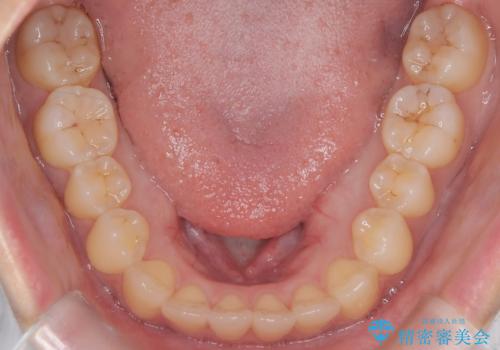

- 前歯のガタガタ(叢生)と、前歯が出ている(突出している)ことを気にされてご来院されました。精密な検査の結果、歯が並ぶスペースと、前歯を引っ込めるスペースの両方が不足していると診断。患者様のご希望に合わせ、透明で目立ちにくいインビザライン(マウスピース矯正)による治療計画を立案しました。スペースの確保は、奥歯全体を奥へ動かす遠心移動と、歯の側面をわずかに削る**IPR(歯間乳頭保護下ストリッピング)**を組み合わせて行い、前歯を効果的に引っ込めることを目指します。

今回の矯正治療では、透明なマウスピース型の装置インビザラインを使用しました。前歯を無理なく引っ込めるスペースを作るため、まず奥歯全体を後方へ移動させる遠心移動を実施。さらに、安全性が確保できる範囲で歯の側面をわずかに削るIPRを併用し、必要なスペースを確保しました。これらの処置により、前歯のデコボコが解消され、前に出ていた前歯も適切に引っ込みました。目立たない装置で治療を完結することで、叢生と突出感が解消され、機能性と審美性が向上した美しい口元を獲得していただけました。